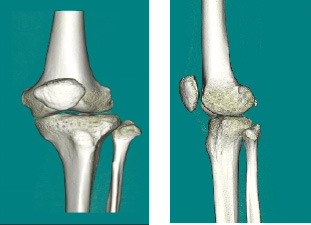

CT装置

- ・輪切りや色々な角度の3D 画像で人体の中を撮影出来ます。

- ・健診~精密検査まで幅広く使用します。

一般撮影の撮影画像

胸とお腹の輪切り画像

3D画像